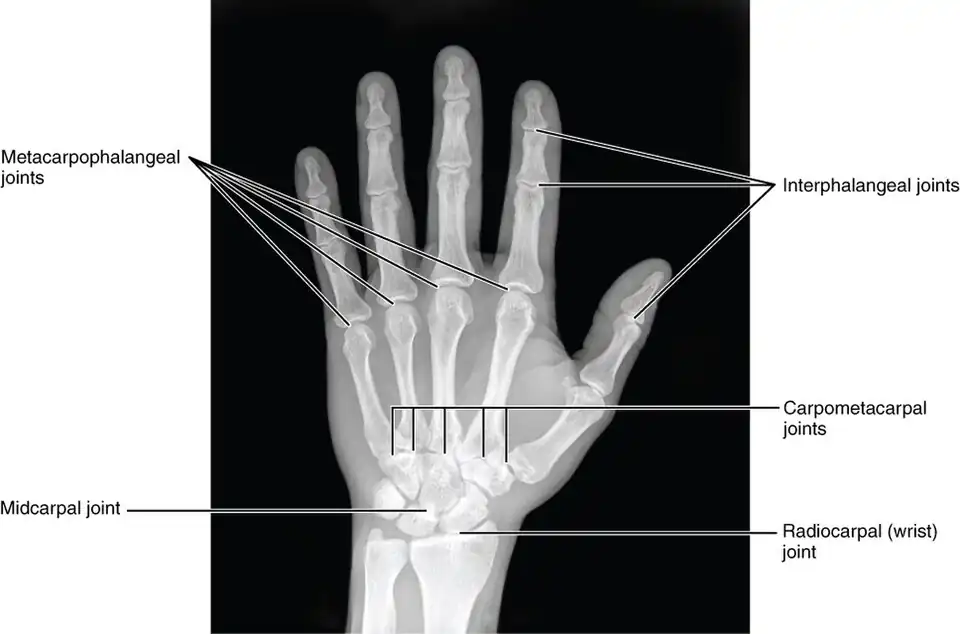

Joints of the hand in an X-ray image -